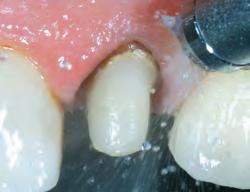

1. Subgingival preparation with bleeding. BLEEDING HEMOSTASIS

2. Scrub Astringedent™ X hemostatic firmly against bleeding tissues with Metal DentoInfusor™ tip.

CLEANING/TESTINGDISPLACEMENT

3. Firm air/water spray removes residual

and tests tissue for quality, profound hemostasis.